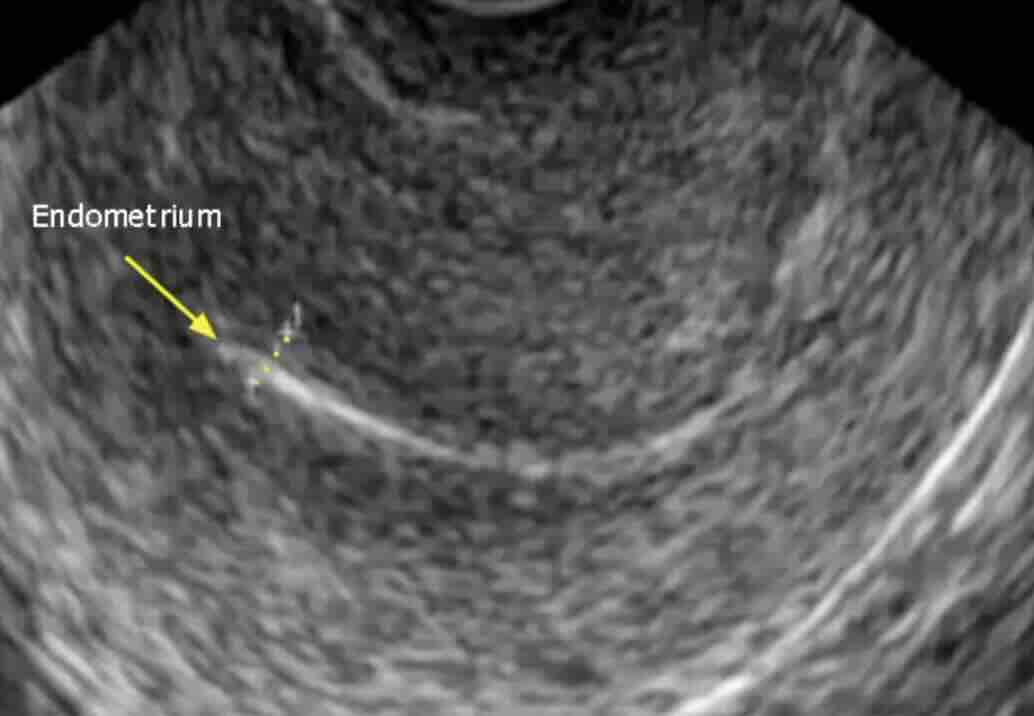

Rahim filmi, rahim iç boşluğunu ve tüplerin açıklığını değerlendirmek için yapılan özel bir röntgen görüntüleme yöntemidir.

Bu işlem sırasında rahim içine kontrast madde verilir ve röntgen altında görüntü alınır. Eğer tüpler açıksa kontrast tüplerden karın içine yayılır. Eğer tıkanıklık varsa kontrast ilerlemez ve bu durum net şekilde görülür.